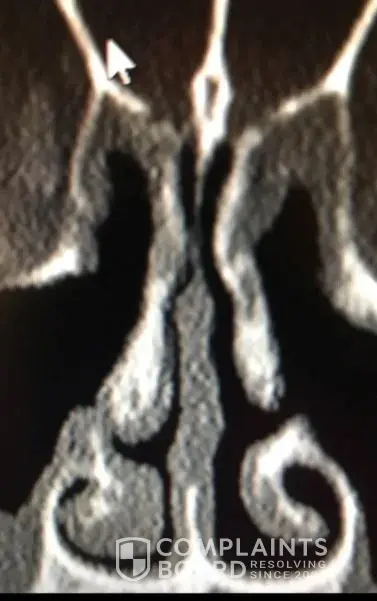

For people reading this, I have included x-ray images of the inside of my nose, before and after my surgery with him. As you can see from these images, my nasal airway was equally open on both sides, before surgery, and the septoplasty didn't need to be done. By performing it, he severely narrowed the right side of my nasal airway.

Dr Raviv performed two surgeries on me: endoscopic sinus surgery (where they widen the sinus passages), and septoplasty (where they straighten the septum). The septoplasty, however was completely unnecessary, and severely narrowed the right side of my nasal airway. For people reading this, I have included x-ray images of my sinuses, before and after my surgery with Dr. Raviv. As you can see from the surgery, my airway was much more open, and equal on both sides, before my surgery with him.